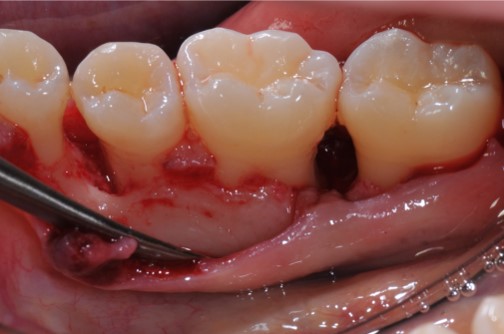

07/22 - Intra-operative view reveals deep non-contained intrabony defects distally to tooth 46 (PPD 10 mm) and on the mesial aspect of tooth 45 (PPD 6 mm). Buccal view.

Deep intrabony defects treated using Straumann® Emdogain® - Dr. M. Stefanini